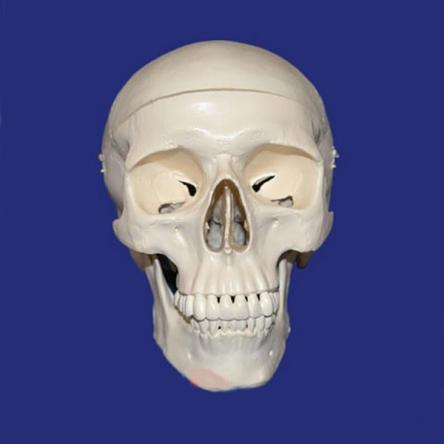

Детальная модель черепа человека A014 в натуральную величину с изображением всех детальных структур. Съемный свод черепа позволяет изучить внутреннее строение. Модель подходит для изучения в медицинских учебных учреждениях.

Эта модель классического черепа объединяет качество, удобство использования с низкой ценой. Наглядное пособие представляет собой высокоточную копию натурального человеческого черепа.

Наша модель не просто состоит из 3-х частей (основной части, крыши и нижней челюсти), но и отличается тем, что имеет съёмные зубы. Нижняя челюсть подвижно соединена с основанием, крыша фиксируется на основании с помощью крючков.

Покупали такую модель в нашу стоматологическую клинику. Благодаря подвижной нижней челюсти можно продемонстрировать работу височно-челюстного сустава. Модель очень реалистична.